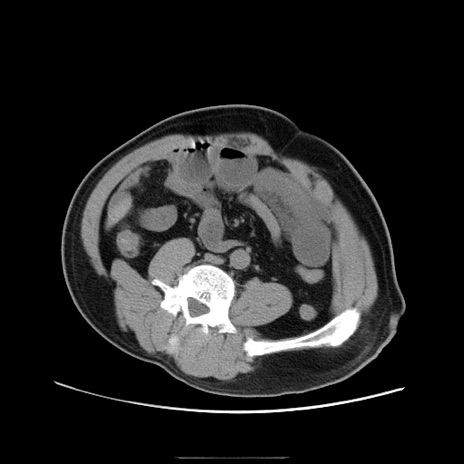

症例22(横断像)

【症例】50歳代男性

【主訴】腹痛

【現病歴】AVMからの被殻出血のため回復期リハ病棟入院中。 本日午後3時頃急に下腹部痛が出現した。

【既往歴】AVM、被殻出血、虫垂炎、高血圧

【身体所見】意識晴明、左半身不全麻痺、会話の理解は良好、36.5°C、腹部:膨隆、全体に板状硬、下腹部正中に圧痛点あり、反跳痛-、筋性防御不明、右下腹部にope scar

【データ】WBC 9400、CRP 0.06